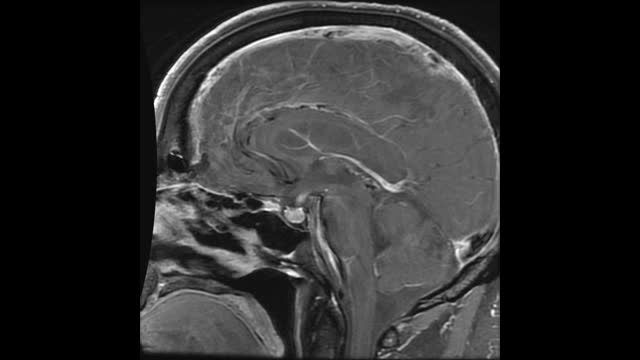

IMAGING - MR brain images show a diffusely thickened pituitary stalk and a larger than expected pituitary gland for age, which are otherwise normal in signal intensity on T1 and T2 weighted images. The gland and stalk both demonstrate avid enhancement on post-contrast imaging. (see image).